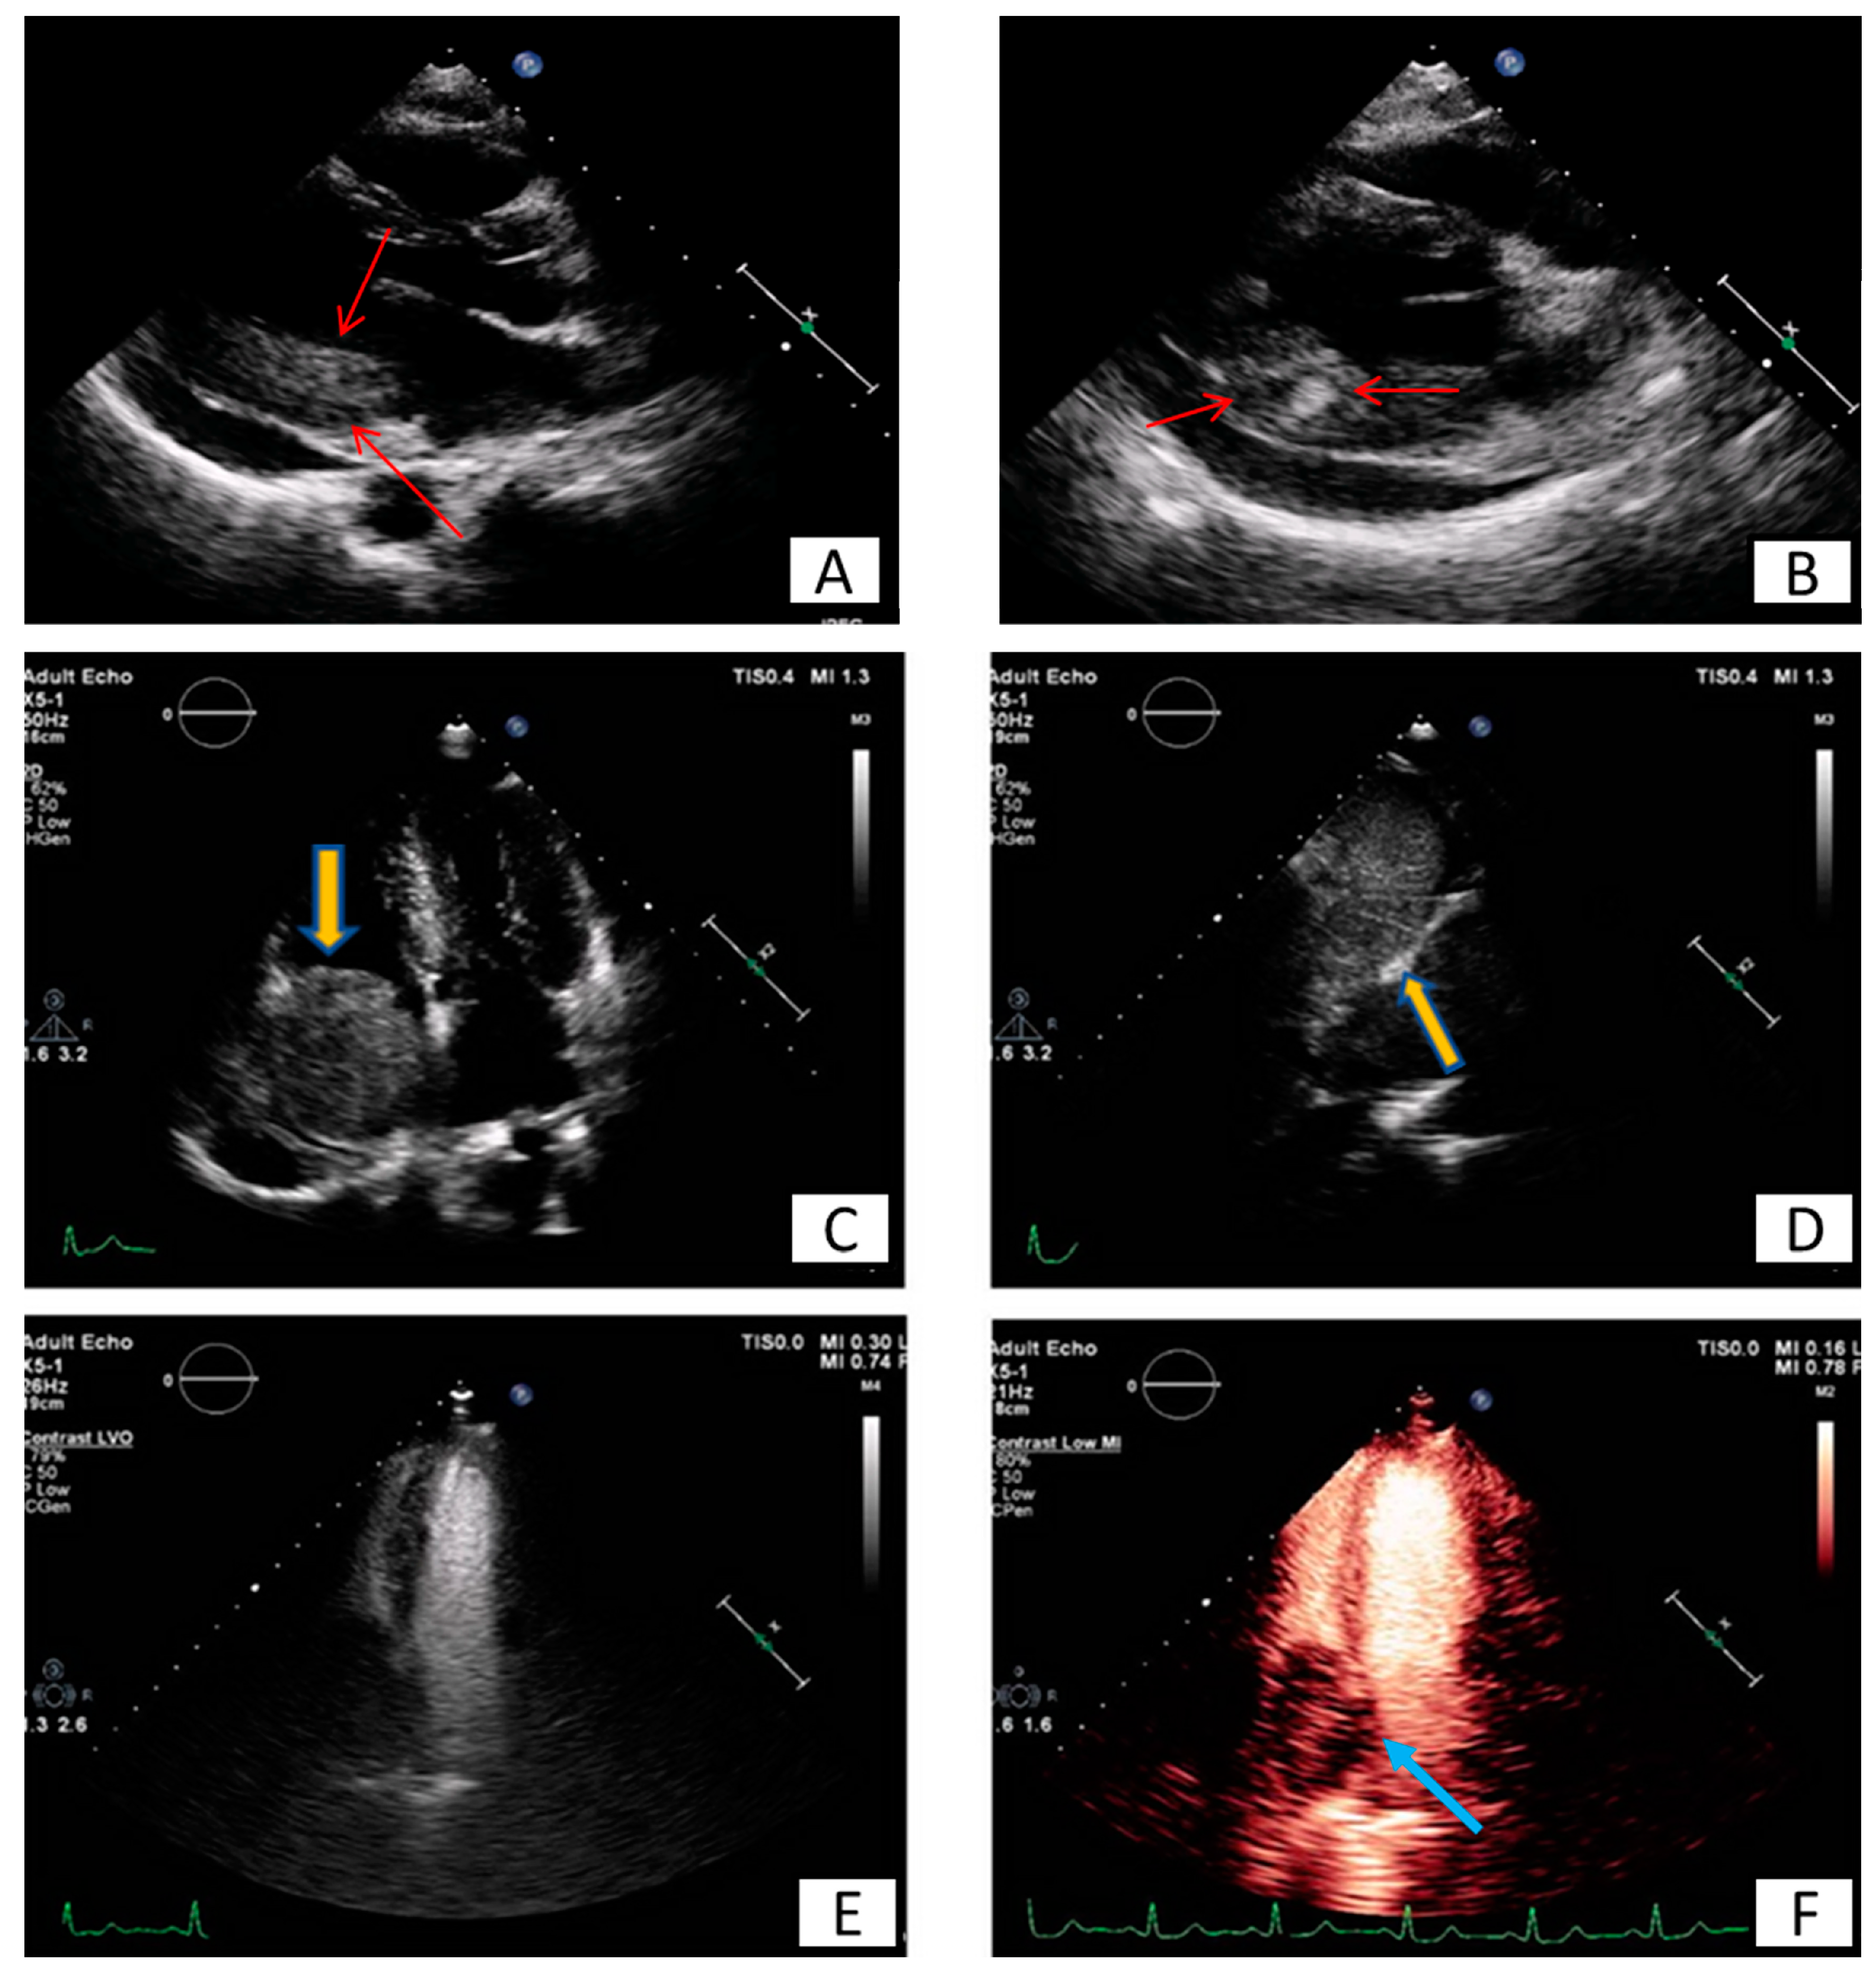

| Common Age at Presentation | Common Location at Heart | Clinical Manifestations | Echocardiography | CT | CMR | |

|---|---|---|---|---|---|---|

| Benign primary heart tumors | ||||||

| Myxoma | Early (familial) or middle adulthood | LA, atrial septum, any other site | Emboli, flow obstruction, systemic symptoms | Mildly lobar, heterogeneous echodensity, usually mobile (with or without stalk) | Heterogeneous, low attenuation, may be calcified | Isointense T1w, High T2w, heterogeneous LGE |

| Papillary fibroelastoma | Middle or late adulthood | Cardiac valves | Usually asymptomatic, emboli | Circular, pedunculated, non-protruding, usually not causing valve dysfunction | Smooth, pedunculated | Iso/hypointense T1w, high T2w, LGE, highly mobile, consider TEE |

| Lipoma | Adulthood | Left ventricle, any other site | Usually asymptomatic, arrhythmias, flow obstruction | Homogeneous | Smooth, homogenous encapsulated, fat attenuation, no enhancement with contrast | High T1w, T2w, no LGE, suppressed with SPIR |

| Rhabdomyoma | Infancy or early childhood | Ventricles, atrioventricular valves | Usually asymptomatic, flow obstruction, heart failure, arrhythmias | Homogenous, slightly echogenic, can be multiple | Attenuation similar to myocardium, intramural | Isointense T1w, iso/hyperintense T2w, no LGE |

| Fibroma | Early childhood | Intraventricular septum, ventricles | Usually asymptomatic, arrhythmias | Heterogeneous, echogenic, non-contractible, can mimic HCM | Soft tissue attenuation, low contrast enhancement, may be calcified | Isointense T1w, Low T2w, high LGE |

| Hemangioma | Any age | Any other site | Usually asymptomatic, dyspnoea | Highly echogenic with contrast infusion, may resemble a cavity | Heterogeneous, high contrast enhancement, may be calcified | Heterogeneous, high T1w, Very high T2w, centripetal progression on first pass, heterogeneous LGE, |

| Malignant primary heart tumors | ||||||

| Angiosarcoma | Early and middle adulthood | RA, pericardium | Constitutional symptoms, heart failure, pericardial effusion | Heterogeneous, highly echogenic with contrast infusion | Heterogeneous, irregular, low attenuation | Heterogeneous T1w, T2w LGE, early enhancement at first pass |

| Rhabomyosarcoma | Childhood, early adulthood | Ventricles, any other site | Heart failure | Normal-high echodensity | Irregular, low attenuation | Isointense T1w, high T2w, usually homogenous LGE |

| UPS/Myxofibrosarcoma | Early and middle adulthood | Left atrium, any other site | Flow obstruction/heart failure, pericardial effusion, metastatic | Heterogeneous, normal-high echodensity | Heterogeneous, low attenuation | Heterogeneous T1w, T2w LGE |

| Lymphoma | Adulthood | RA, any other site | Pericardial effusion, flow obstruction/heart failure | Any size and shape | Normal to low attenuation, heterogeneous contrast enhacncement | Isointentse T1w, T2w, minimal LGE |

| Mesothelioma | Adulthood | Pericardium | Pericardial effusion | Heterogeneous | Variable characteristics | Isointense T1w, Heterogeneous T2w, high LGE |

| Metastatic tumors | ||||||

| Melanoma | Adulthood | Any site | Flow obstruction/heart failure, pericardial effusion | Heterogeneous, highly echogenic with contrast infusion | Similar to soft tissue, hard to recognize | High T1w, low T2w heterogeneous LGE |

| Other metastatic tumors | Adulthood | Pericardium, any site | Flow obstruction/heart failure, pericardial effusion | Heterogeneous, highly echogenic with contrast infusion | Solid, similar to soft tissue attenuation, moderate to high contrast enhancement | Low T1w, high T2w, heterogeneous LGE |

| Non-neoplasmatic heart masses | ||||||

| Clots | Adulthood | LAA, LV apex | Emboli | Acute: Low echodensity Chronic: High echodensity No perfusion with contrast agents | No contrast enhancement, may be calcified | No EGE/LGE Acute: Isointense to high T1w, T2w Subacute: High T1w, Low T2w Chronic: Low T1w, T2w |

| Vegetation | Adulthood | Cardiac valves | Valve dysfunction, emboli, heart failure | Highly mobile, oscillating protruding, valve dysfunction, | Low attenuation, may recognize, perivalvular extension, fistulas, abscess | Highly mobile, consider TEE |

| Non-neoplasmatic calcified masses | Adulthood | Usually posterior mitral annulus | Usually asymptomatic | Very high echodensity | Heterogeneous, calcified | Signal loss, consider CT |

| Pericardial cysts | Adulthood | Pericardium | Usually asymptomatic, external compression | Low echodensity, typically no perfusion with contrast agents | Presence of wall, fluid attenuation | Depends on the fluid, usually isointense T1w, high T2w, no LGE |

| Lipomatous Hypertrophy | Late adulthood | Atrial septum | Usually asymptomatic, arrhythmias | Homogeneous dumbbell appearance of atrial septum | Fat attenuation | High T1w, T2w, no LGE, suppressed with SPIR |